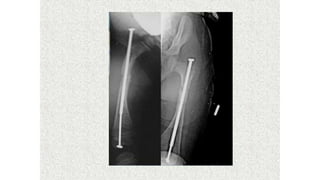

This document discusses a disease and its investigation and management. It begins by introducing Dr. Aniket Wankhede from MGIMS Sevagram and asks what the disease is. It then asks how the disease happens and discusses its causes. Next it asks how the disease appears on x-rays and describes symptoms some people experience living with it. Finally, it asks how the disease will be investigated and managed.